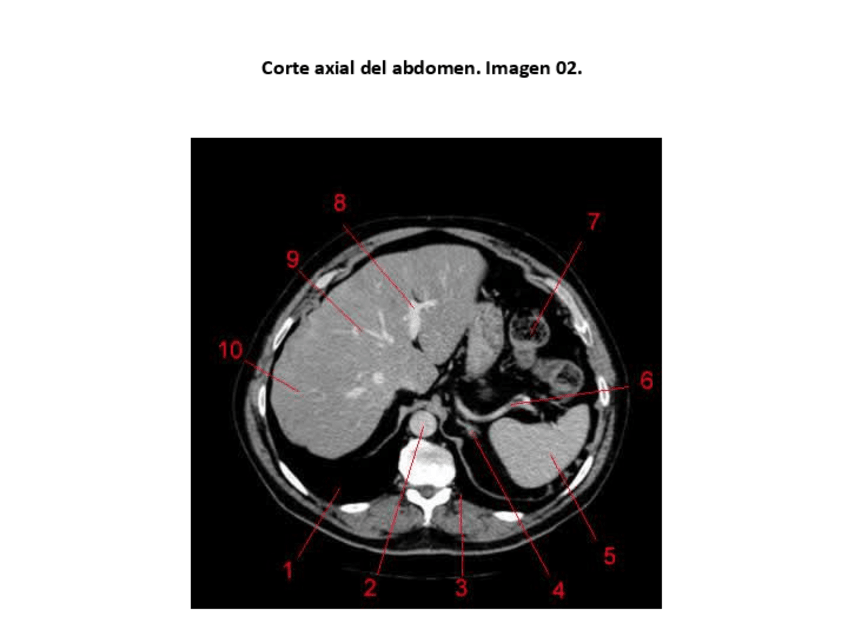

Imágenes de prácticas con respuestas

He publicado nuevos practicas de 3º Anatomía Humana a Través de la Imagen: Imágenes de prácticas con respuestas